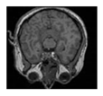

This section contains extensive performance evaluation findings for the three suggested approaches. The developed systems were tested over Matlab environment. As shown in Figure 6, the suggested encryption techniques have been tested for color, grayscale, and medical photos, each of which is 256 × 256 pixels in size, with watermarks of 64 × 64 pixels.

Figure 6.

Color, grayscale and medical images and watermarks.